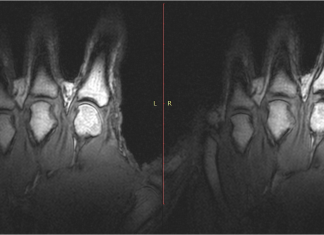

Video: dit gebeurt er als je je vingers knakt

De krakende geluiden afkomstig uit synoviale gewrichten ontstaan tijdens door het optreden van gasvorming wanneer de gewrichtsoppervlakken worden gescheiden. Gregory Kawchuk, een bio-ingenieur en revalidatiegeneeskunde specialist aan de...